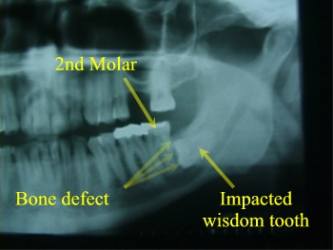

Most people have a set of 32 adult teeth. In a significant number of people, there is not enough ‘room’ in the jaws to permit the very back molars, or wisdom teeth, to erupt into a proper, healthy, position (figure 1). This can result in misaligned wisdom teeth that are able to only partially erupt through the gums, or even not erupt at all. These teeth are described as ‘impacted’. The wisdom teeth may also erupt through the gums, but still remain in a poor position because of their inclination or of the way the gum sits around the tooth. These teeth are considered to be ‘malpositioned’. Impacted and malpositioned wisdom teeth both, can lead to gum and tooth disease as well as other worse jaw disease (see below).

Radiograph of Impacted Wisdom Tooth

Wisdom Tooth Resorbing 2nd Molar

Impacted Wisdom Tooth Causing Cavity and Bone Loss at the Back of the 2nd Molar

Deep Horizontal Impaction with Bony Defect Behind 2nd Molar